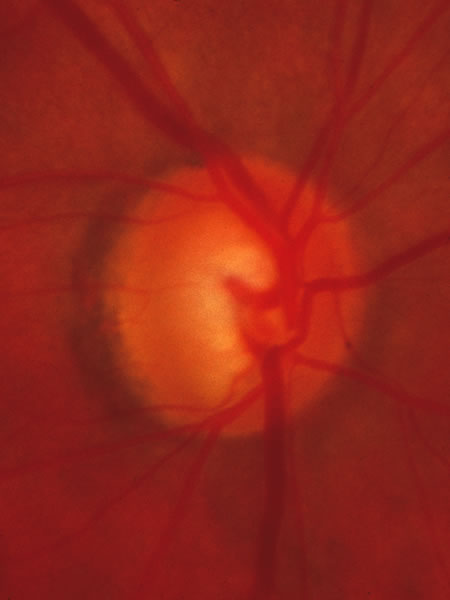

Fig. 33. Swollen disc tissue during an acute attack of angle closure glaucoma.

In acute angle-closure glaucoma (Fig. 33), the optic disc may swell,147–149 perhaps as a result of ischemia, but because of corneal edema and preoccupation with the angle status, it is not often seen. Even after an attack lasting several days, there is often no visual loss; the disc may remain normal appearing or may develop some degree of pallor resembling that of nonglaucomatous optic atrophy.150–152 Excavation of the disc does not seem to result from an acute attack but may result from persistent residual pressure elevation after the attack. If excavation is already present at the time that a patient presents with symptomatic angle closure, the cupping is evidence that for some time an asymptomatic, perhaps gradual, rise of intraocular pressure elevation preceded the abrupt onset of symptoms.